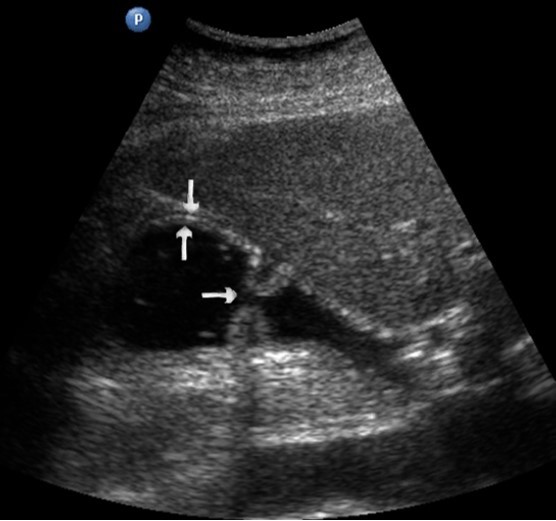

Distal gastric cancer was observed in 24 (39,3%) cases and contributed to the development of pyloric stenosis: in 6 (9,8%) cases it was compensated, in 18 (29,5%) – was sub compensated. The layers of the wall were not differentiated in all patients with sub compensated pyloric stenosis. In the case of compensated pyloric stenosis, the thickness of the affected area was 10,2±2,9mm, the length was 27,1±6,2mm, the diameter of the pylorus was 8,3±0,8mm (Figure 14). Among patients with sub compensated pyloric stenosis, the thickness of the stomach wall was 19,8±4,1mm, the length was 43,6±4,5mm, the pyloric diameter was 4,3±1,1mm (Figure 15).

Figure 14.Gastric carcinomas of diffuse infiltrative form in the atrium of T2 stage. Compensated pyloric stenos. On an empty stomach in the cavity of the stomach is determined an a small amount of fluid. The diameter of the pyloric canal more than 7 mm.

Figure 15.Distal gastric carcinomas of diffuse infiltrative form of T3 stage. Sub compensated pyloric stenos (arrows). The thickness of the anterior wall of the stomach is 9,13 mm, extent of the affected area – 7,84 cm. On an empty stomach in the cavity of the stomach is determined an a large amount of fluid. The diameter of the pyloric canal is about 6 mm.